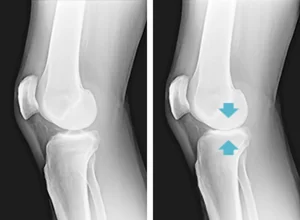

Increasing Body Weight Puts Strain On Knee Joints